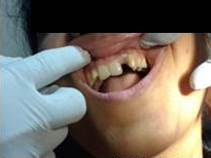

Use of Bone Graft & GTR membrane for an Implant

Pre Operation